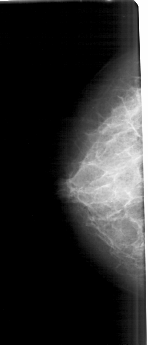

A_1682_1.LEFT_MLO

LEFT_MLO LINES 5491 PIXELS_PER_LINE 2476 BITS_PER_PIXEL 12 RESOLUTION 43.5 NON_OVERLAY